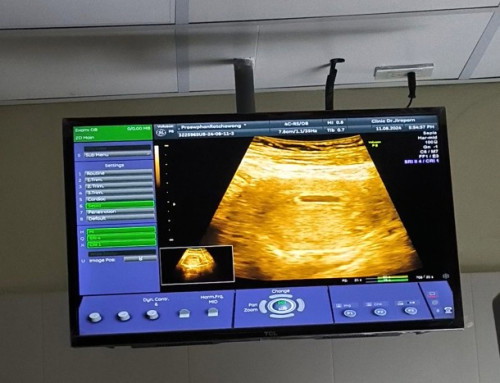

วันนี้ไปซาว์มาครับหมอบอกเจอแต่ถุงไข่แดง อาจจะยังครรภ์อ่อนอยู่ ตอนนี้หมอบอกประมาณ5สัปดาห์ อีก2อาทิตย์ให้ไปซาว์ใหม่

ปกติค่ะ เจะห็นน้องได้แบบชัดๆน่าจะประมาณ10วีคนะค่ะ เพราะตอนนี้ท้องยังอ่อนอยู่ค่ะ